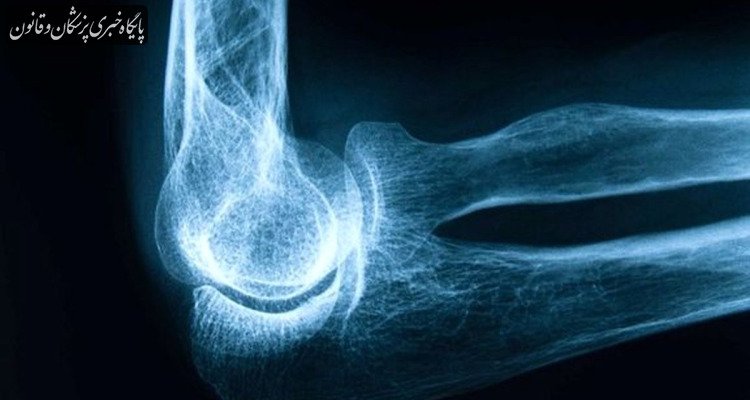

رکنا: متخصص ارتوپدی و عضو هیات علمی دانشگاه علوم پزشکی البرز با اشاره به روند خاموش و تدریجی بیماری پوکی استخوان گفت: فرآیند کاهش تراکم استخوان معمولاً از سن ۳۰ سالگی به بعد آغاز میشود، بهویژه در خانمها پس از یائسگی و در آقایان از حدود ۶۵ سالگی به بعد شدت بیشتری پیدا میکند.

به گزارش پایگاه خبری پزشکان و قانون (پالنا)، محمد شیبانی گفت: پوکی استخوان بیماریای است که بهتدریج استخوانها را شکننده و مستعد شکستگی میکند. از آنجا که اغلب بدون علامت است گاهی نخستین علامت آن یک شکستگی ناگهانی پس از ضربه خفیف یا حتی بدون ضربه است.